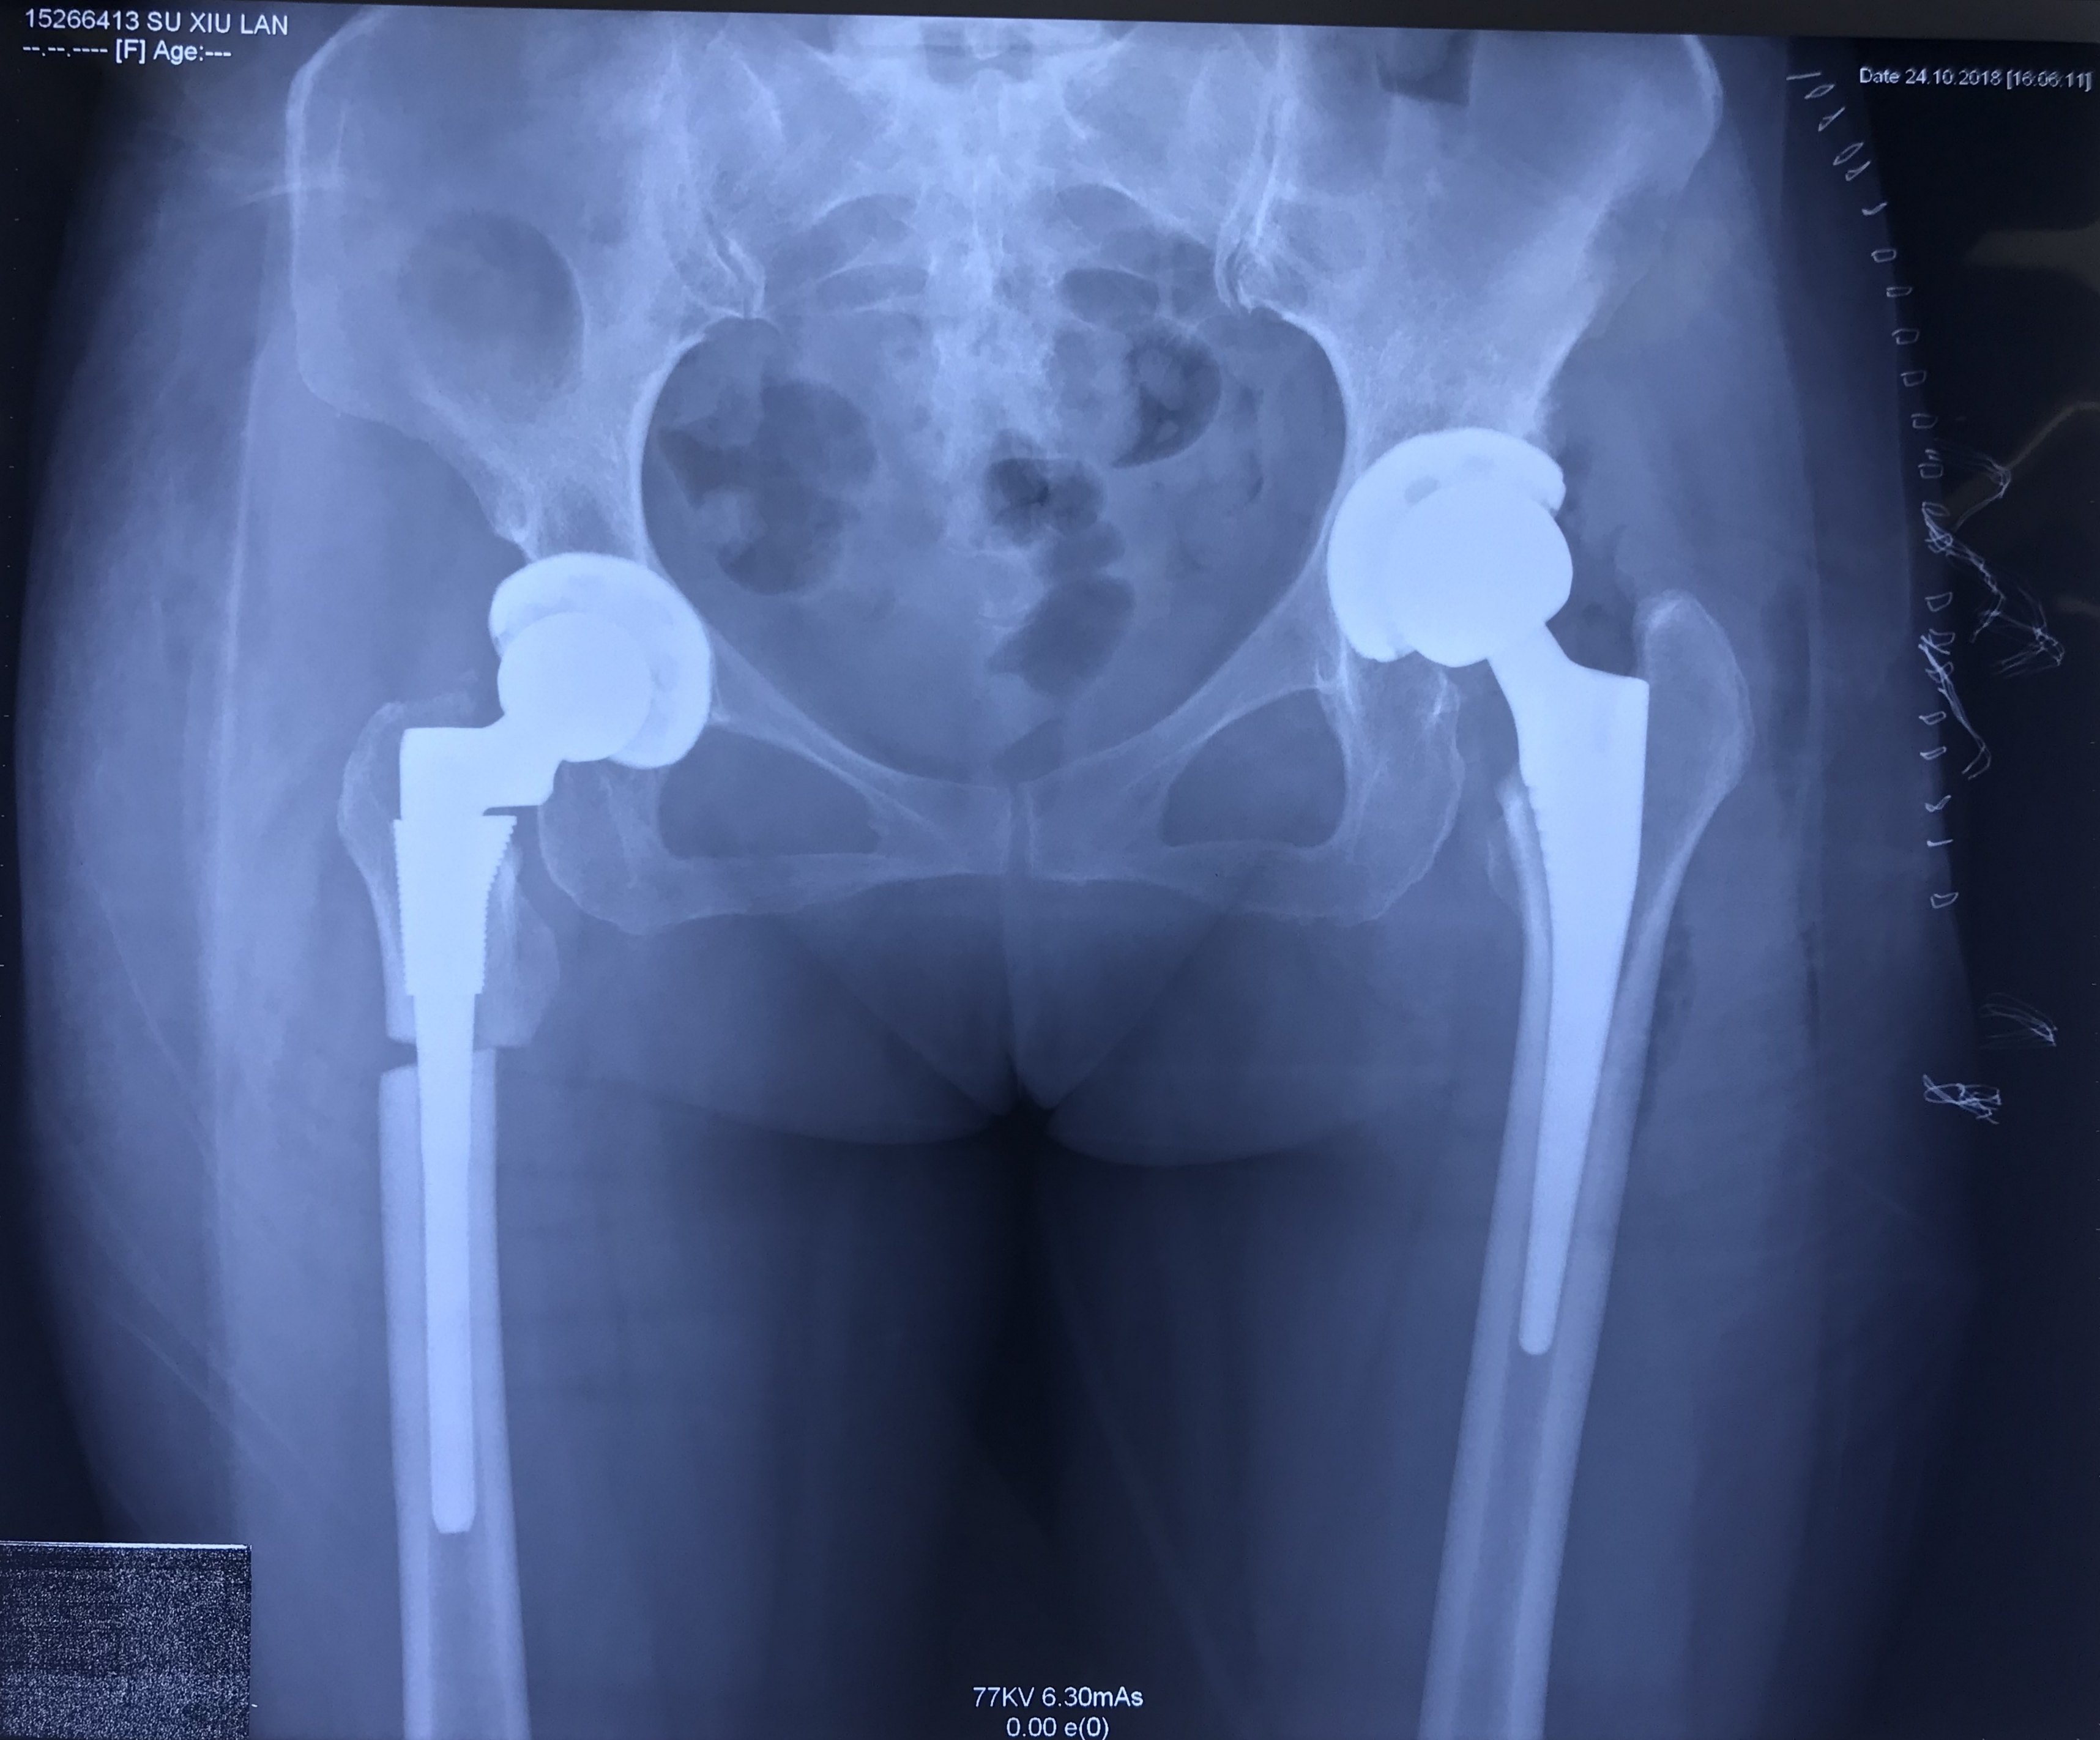

病例 4 64岁女性,四型髋关节发育不良,合并骨质疏松,大骨节病,s-rom